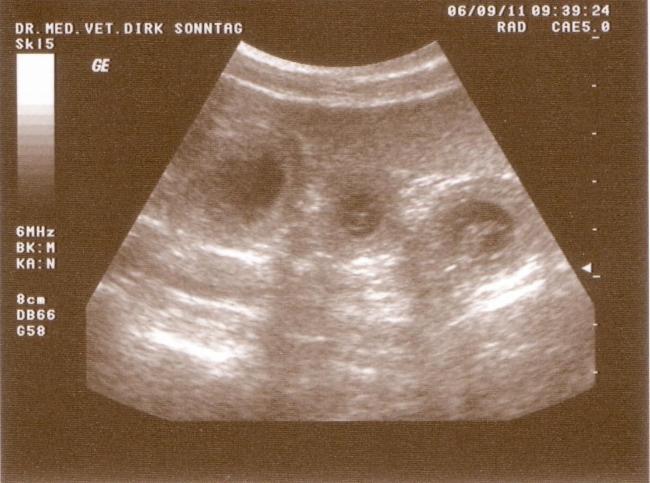

06.09.2011 Die Ultraschalluntersuchung

Der 26. Tag der Trächtigkeit war auch der Tag der Ultraschalluntersuchung. Er zeigte was ich schon lange wusste: Elena trägt die B-chen in sich. 10 Welpen konnten wir auf Anhieb entdecken. Wie viele es wirklich werden, wird Elena erst Mitte Oktober veraten, doch wer sich an den Ultraschall des A-Wurfes erinnert, kann sich denken das sich da vermutlich noch mehr B-chen in Elenas Bauch versteckt haben.

Jetzt darf man sich auf Bella, Balou Junior, Bailey, Betty-Lou, Baby-Lee und wie sie alle heißen sollen freuen!

Stellvertretend für die anderen B-chen stellen wir hier schon mal die ersten vor: